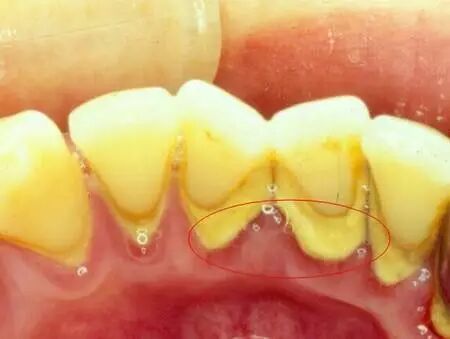

有效地预防牙周病:人的唾液中溶解了很多矿物质,日积月累的沉积在牙齿上就形成牙结石,也叫牙石。牙结石粘附在牙齿颈部或牙龈下根部,质地坚硬,牙结石藏污纳垢,滋生的各种病菌产生的毒素能刺激牙龈,引起牙龈发炎、红肿、出血,进而引起牙龈萎缩,是造成牙周病的主要原因,还会引起口臭。刷牙等一般方法去除不掉牙结石。只有通过洗牙才能够有效地去除牙结石,保护牙周组织。

洗牙就是指医生通过口腔科专门的器械把我们牙齿表面的牙菌斑,牙结石等清除掉,对于牙周炎和牙龈炎有很好的预防和治疗作用,从而保证我们拥有健康口腔。